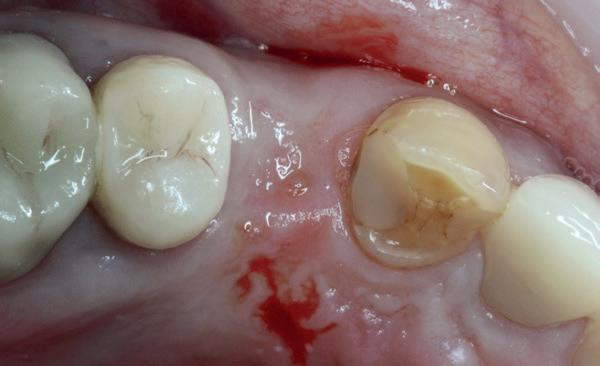

De aanleiding: waarom brak de kies?

De patiënt kwam bij mij in de praktijk met een afgebroken eerste premolaar 24. Op het eerste gezicht leek het een typische casus van structurele verzwakking, mogelijk door een oude restauratie of een occlusale overbelasting. Maar een nadere analyse toonde een veel fundamenteler probleem: er was geen hoektandgeleiding aanwezig.

Normaal gesproken neemt de cuspidaat de functie van disclusie over bij laterale bewegingen, waardoor premolaren en molaren worden ontzien van over-

matige zijwaartse krachten. Bij deze patiënt functioneerde de eerste premolaar echter als een canine, wat betekende dat hij continue laterale belasting kreeg waarvoor hij simpelweg niet ontworpen was. De breuk was dan ook geen toeval, maar een voorspelbare mechanische uitkomst van een verkeerde krachtenverdeling.

In een ideale situatie zou ik eerst de occlusale verhoudingen corrigeren voordat ik een implantaat plaatste. Maar zoals vaak in de praktijk, had de patient een duidelijke wens: een snelle, vaste oplossing, zonder aanvullende restauratieve behandelingen zoals het herstellen van de hoektandgeleiding.

1. Afgebroken 24. Geen hoektandgeleiding aanwezig.

De implantaatplaatsing en de beslissende fout (afbeelding 1-13)

De extractie verliep voorspoedig, waarbij ik zoals al-

tijd probeerde de buccale botlamel intact te houden. Dit is cruciaal voor latere botbehoud en implantaatplaatsing. Na curettage en spoelen van de alveole beoordeelde ik de situatie opnieuw: de botcondities leken gunstig voor een immediaat implantaat.

Hier begon echter de cruciale fout in mijn klinisch besluitvormingsproces. In mijn streven naar maximale primaire stabiliteit - wetende dat immediaat belasten enkel mogelijk is bij hoge stabiliteit -on-

derprepareerde ik de osteotomie. Dit betekende dat ik een iets te smal implantaatbed creëerde, in de hoop dat het implantaat stevig in het bot verankerd zou worden.

Op papier leek dit een logische stap: het MegaGen AnyRidge-implantaat dat ik koos, gaf me een stabiliteit van 60Ncm—een cijfer dat vertrouwen gaf in immediaat belasten. Maar in mijn enthousiasme had ik onvoldoende rekening gehouden met de biologische gevolgen van overmatige compressie.

Door de te hoge druk op het omringende bot verminderde daarin de doorbloeding, wat leidde tot een verhoogd risico op botnecrose. Dit was geen fout van abutmentkeuze of occlusie; dit was puur het gevolg van mijn drang naar optimale stabiliteit en de wens om het implantaat direct te belasten, onder invloed van patiëntdruk.

Tijdens de behandeling leek alles goed te gaan. De patiënt verliet tevreden de praktijk met een direct belaste tijdelijke kroon. Maar zes weken later kwam zij terug.